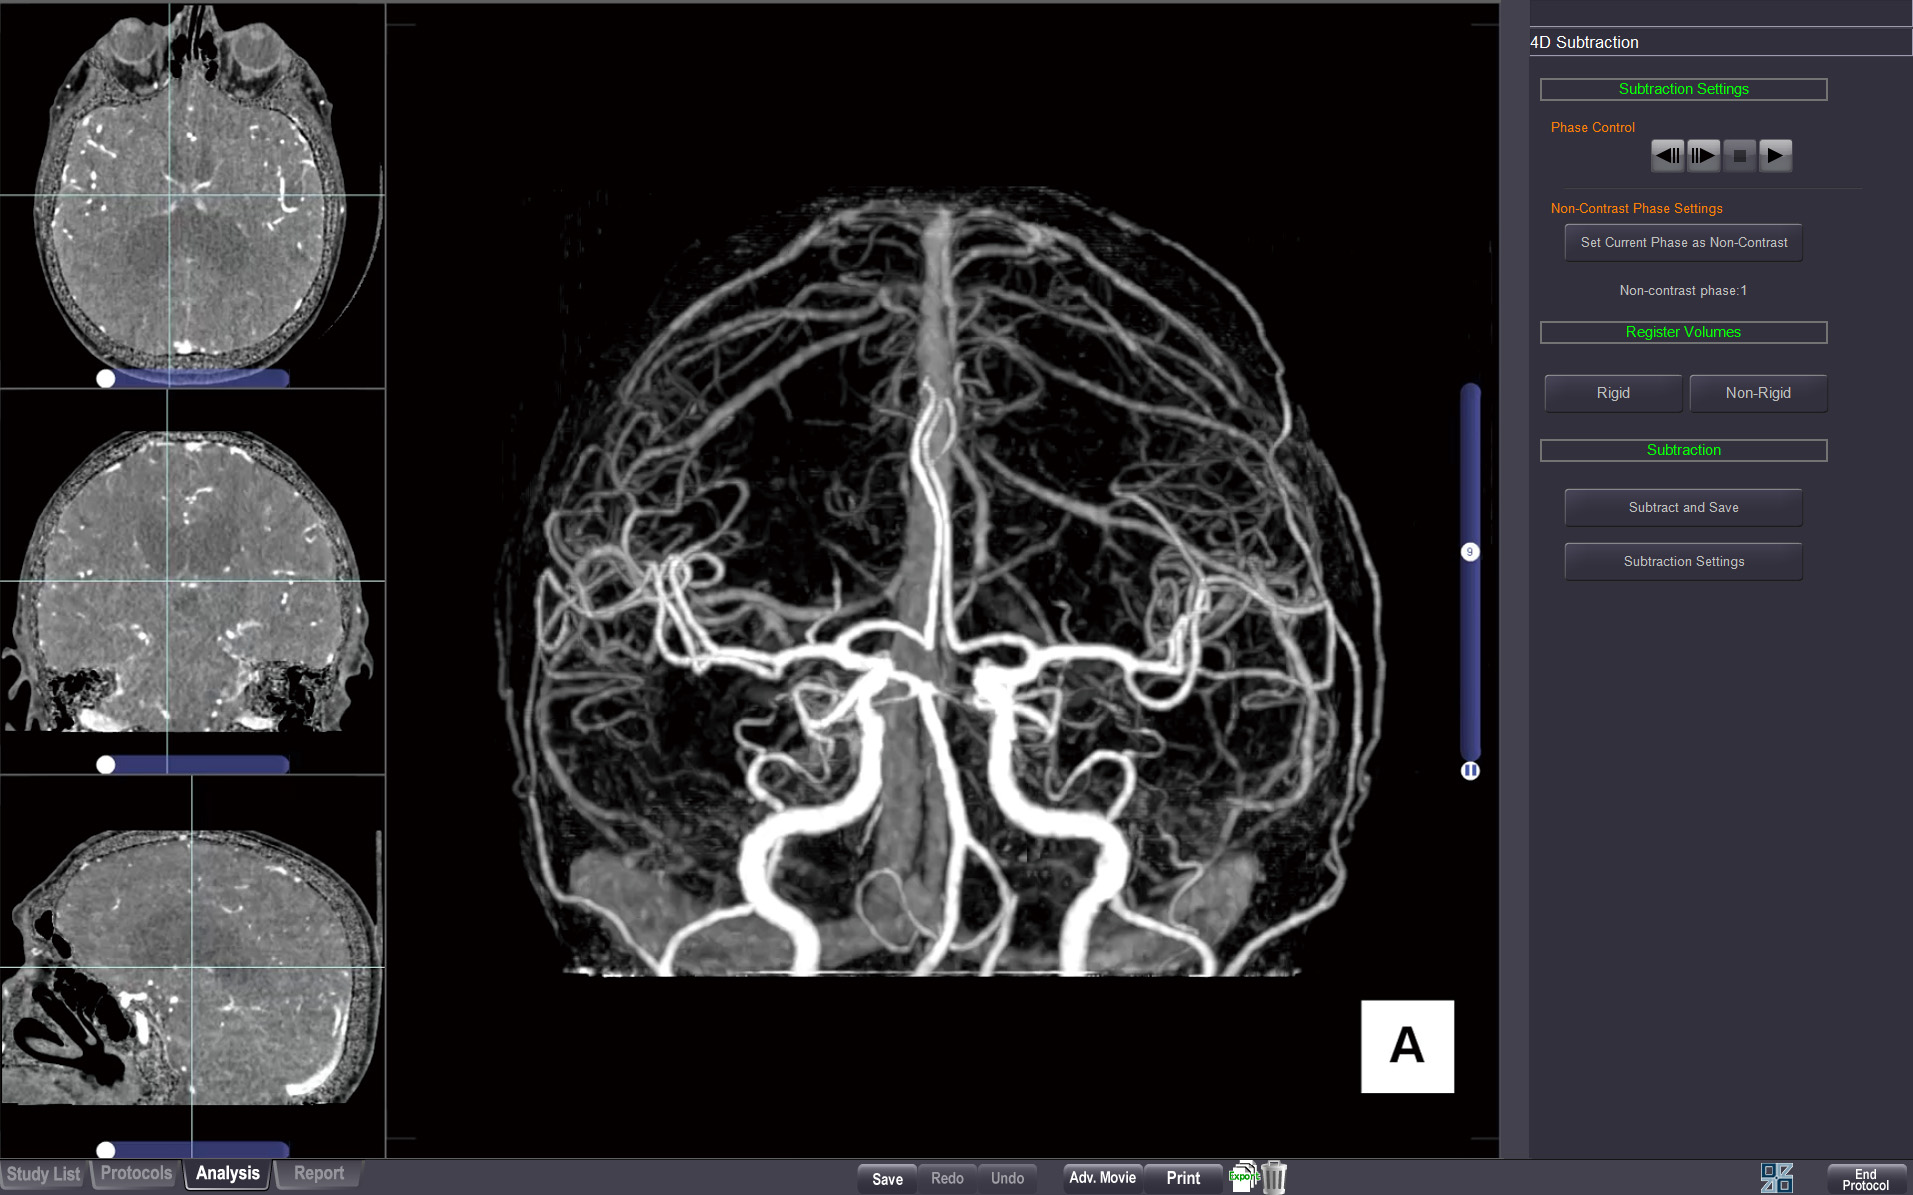

4D SUBTRACTION

The 4D Subtraction protocol creates image subtraction series from dynamic multi-phase CT datasets, enabling true 4D angiographic visualization of vascular flow and anatomy.